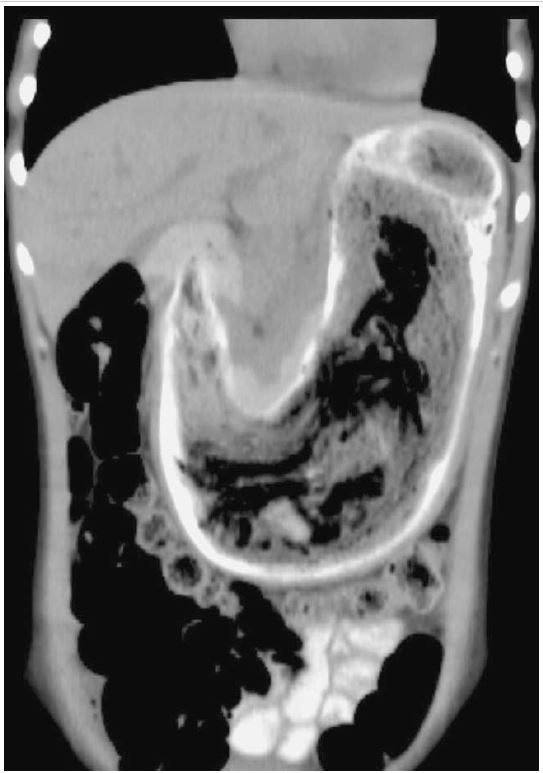

Obstruction due to small bowel bezoar Image Radiopaedia/Bezoar Endoscopy Findings on radiographs can indicate the presence of bezoars, and barium studies can confirm it [1]. According to some recent publications, sonography and ct can be useful in diagnosing bezoars before surgery [2, 3, 4, 5, 6]. The treatment of bezoars depends on their volume, chemical synthesis, location and associated pathology. Bezoar formation in the gastric pouch. Bezoars are known. Radiopaedia/Bezoar Endoscopy.

Small bowel obstruction bezoar Image Radiopaedia/Bezoar Endoscopy According to some recent publications, sonography and ct can be useful in diagnosing bezoars before surgery [2, 3, 4, 5, 6]. The treatment of bezoars depends on their volume, chemical synthesis, location and associated pathology. Findings on radiographs can indicate the presence of bezoars, and barium studies can confirm it [1]. Bezoars are known to cause small bowel obstruction and. Radiopaedia/Bezoar Endoscopy.